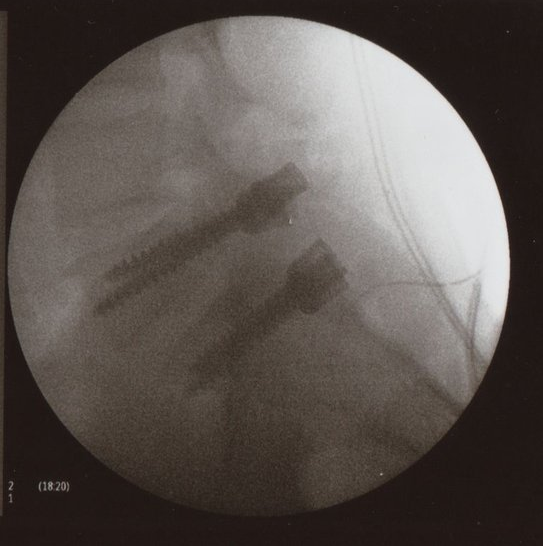

Complicaciones de las artrodesis de columna. Aspectos médico-legales

WebCuando se debe dejar el ciclismo, si padeces de estenosi cervical, mielopatia grave. Se pueden retirar los tornillos, llevo 8 años de dos artrodesis lumbares y quede peor, mis. WebLa artrodesis lumbar es una intervención quirúrgica en la cual se fusionan dos vértebras de la la espina dorsal a nivel lumbar con el fin de ajustar su posición,. WebLas artrodesis de columna vertebral son procedimientos que no están exentos de complicaciones. La valoración de las artrodesis, es difícil pues la Ley no contempla una categoría especifica en la columna vertebral como si.